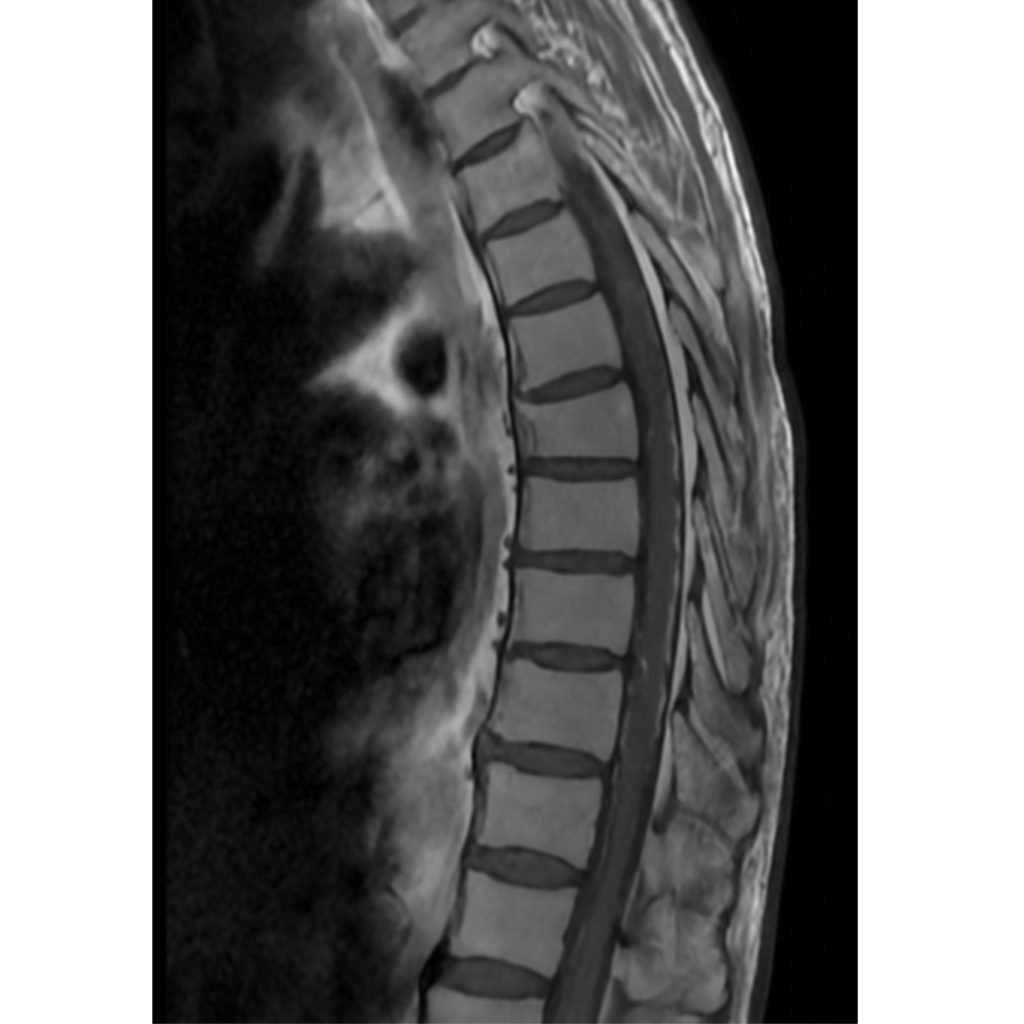

تمكّن الفريق الطبي في وحدة القسطرة بالمستشفى التخصصي، بقيادة الدكتور حازم حبوب استشاري الاشعة التداخلية، من إجراء تداخل طبي متقدم لمعالجة حالة شلل طرفي ناتج عن وجود تشوه شرياني وريدي في النخاع الشوكي، وذلك تحت المراقبة الفسيولوجية العصبية الدقيقة.

وتمت العملية بنجاح من خلال استحضار الإمكانيات الحسية والحركية للمريض أثناء الإجراء، لتفادي أي مضاعفات محتملة.

وأسفرت العملية عن تحسن ملحوظ في حالة المريض، حيث أصبح قادراً على المشي بشكل أفضل وبمفرده، إضافة إلى استعادته السيطرة الكاملة على وظائف الجهاز الهضمي.